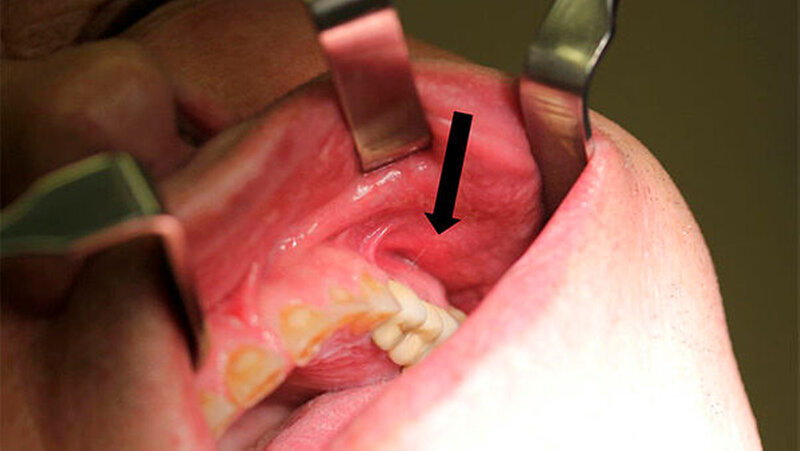

Die klinische Untersuchung zeigte intraoral eine derbe, druckdolente, nicht verschiebliche, abgekapselte Schleimhautschwellung vestibulär regio 23 bis 27 (Abbildung 2) mit putridem Ausfluss aus einem Fistelgang nach extraoral im Bereich der Oberlippe links.